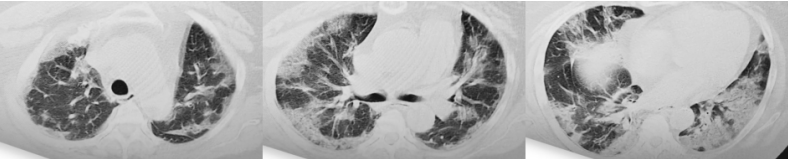

图片

1周后复查胸部CT可见双上肺新发磨玻璃影,双下肺实变为著,影像学较前进展。

2022年12月18日

2022年12月26日